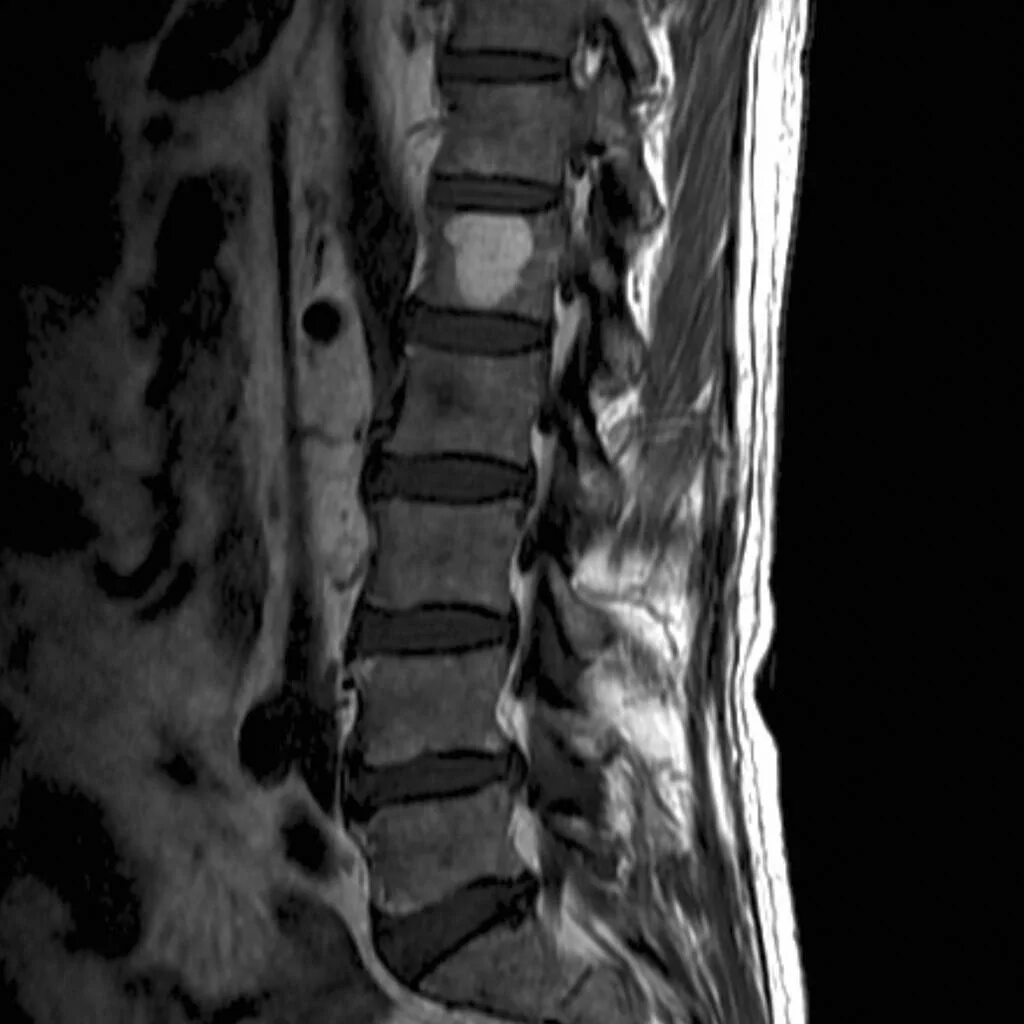

Метастазы в поясничном позвоночнике